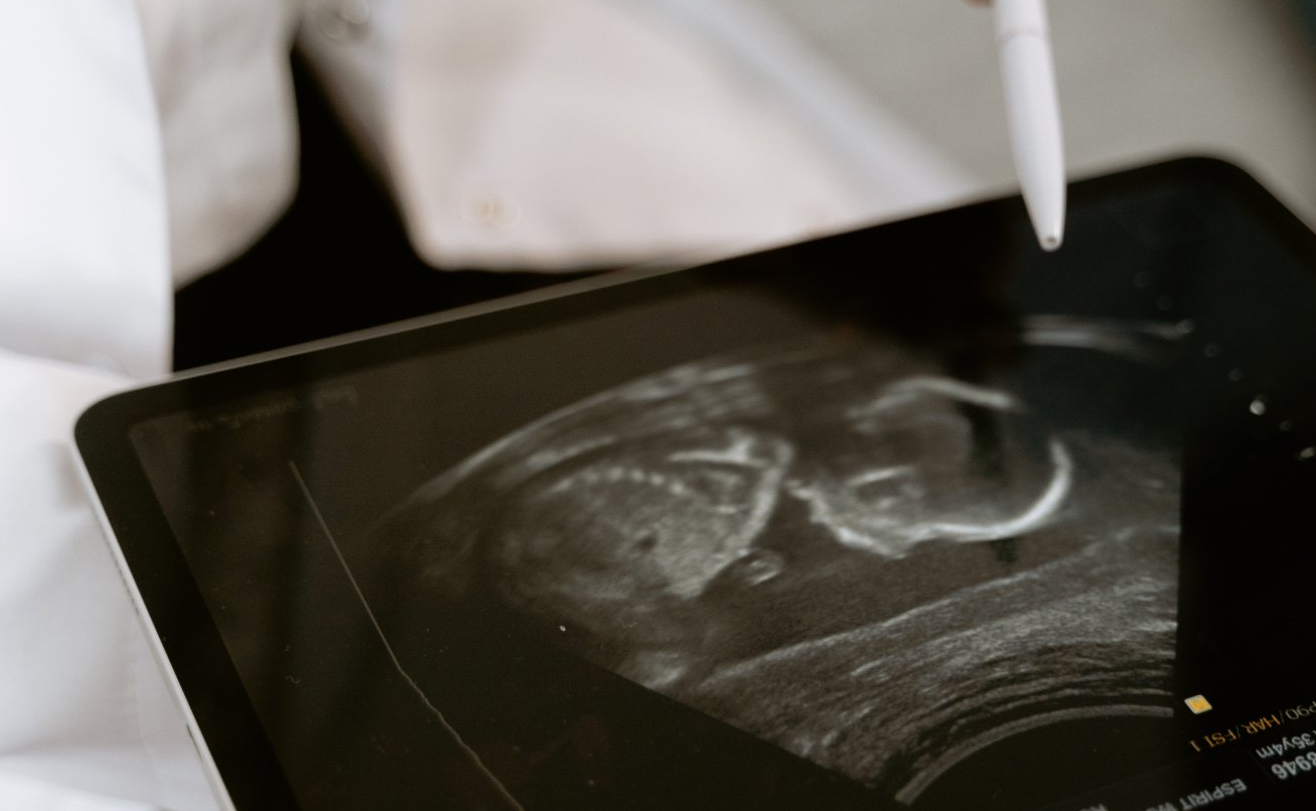

Mobile Ultrasound

Expand your service line without adding complexity, overhead, or staffing challenges.